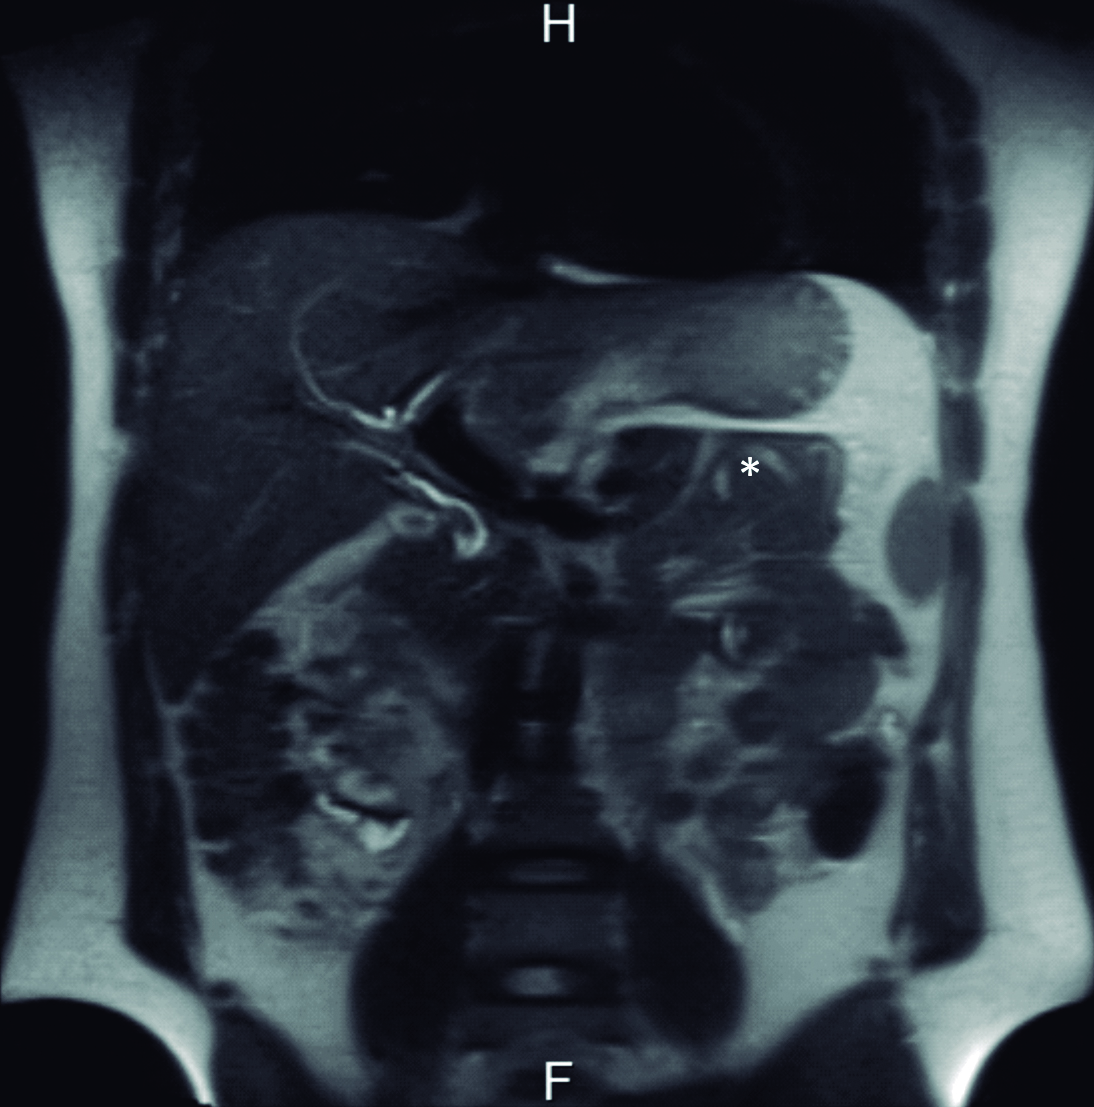

Se interroga a la paciente y refiere haber sido estudiada previamente con una colangiografía por resonancia magnética tres meses previo a la consulta en otro centro hospitalario. En ese momento la vía biliar principal no estaba ocupada. Retrospectivamente se identificaron los parásitos en el tubo digestivo proximal (Fig. 4 y 5).

Figura 5. Colangiografía por Resonancia Magnética - Reconstrucción

Se visualiza vía biliar intra y extrahepática de calibre habitual, sin defectos de relleno.

La resonancia magnética es una excelente modalidad no invasiva para diagnosticar la presencia de parásitos en la vía biliar. En imágenes ponderadas en T1, los gusanos se ven como estructuras tubulares lineales ligeramente hiperintensas con un área central hipointensa y en la colangiografía por resonancia se visualizan como defectos lineales de relleno hipointensos en el tracto biliar. (4, 9, 10)